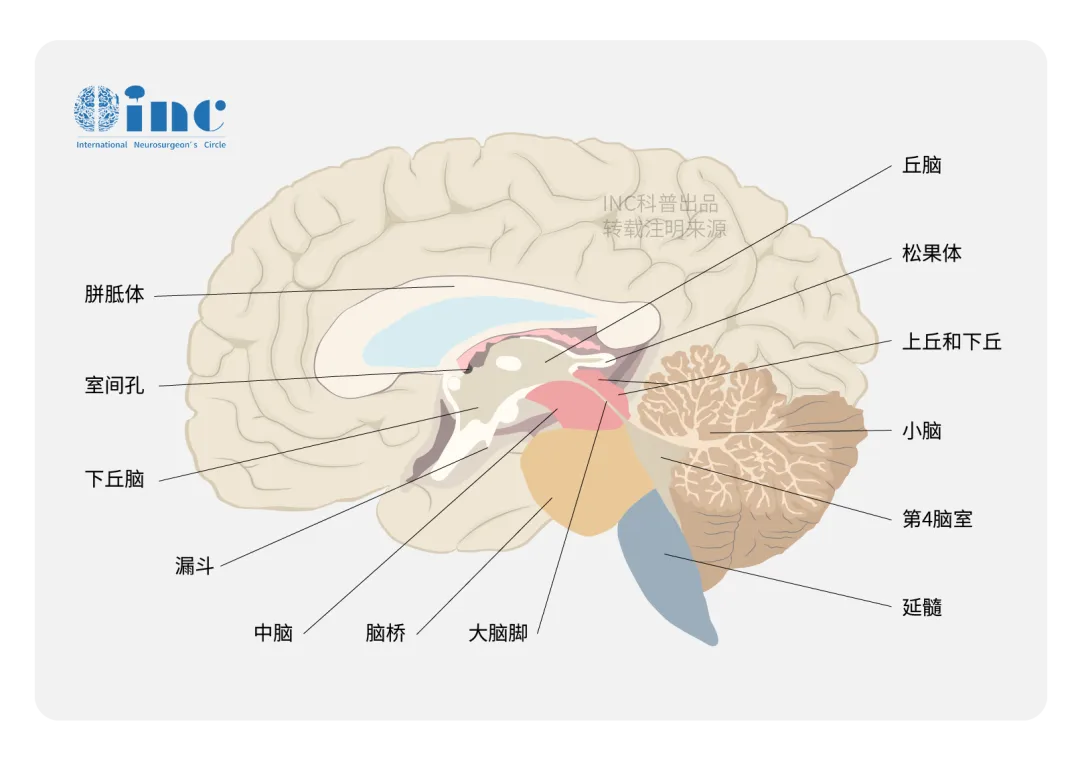

下丘脑不仅通过神经和血管途径调节脑垂体前、后叶激素的分泌和释放,而且还参与调节自主神经系统,如控制水盐代谢、调节体温、摄食、睡眠、生殖、内脏活动以及情绪等。...